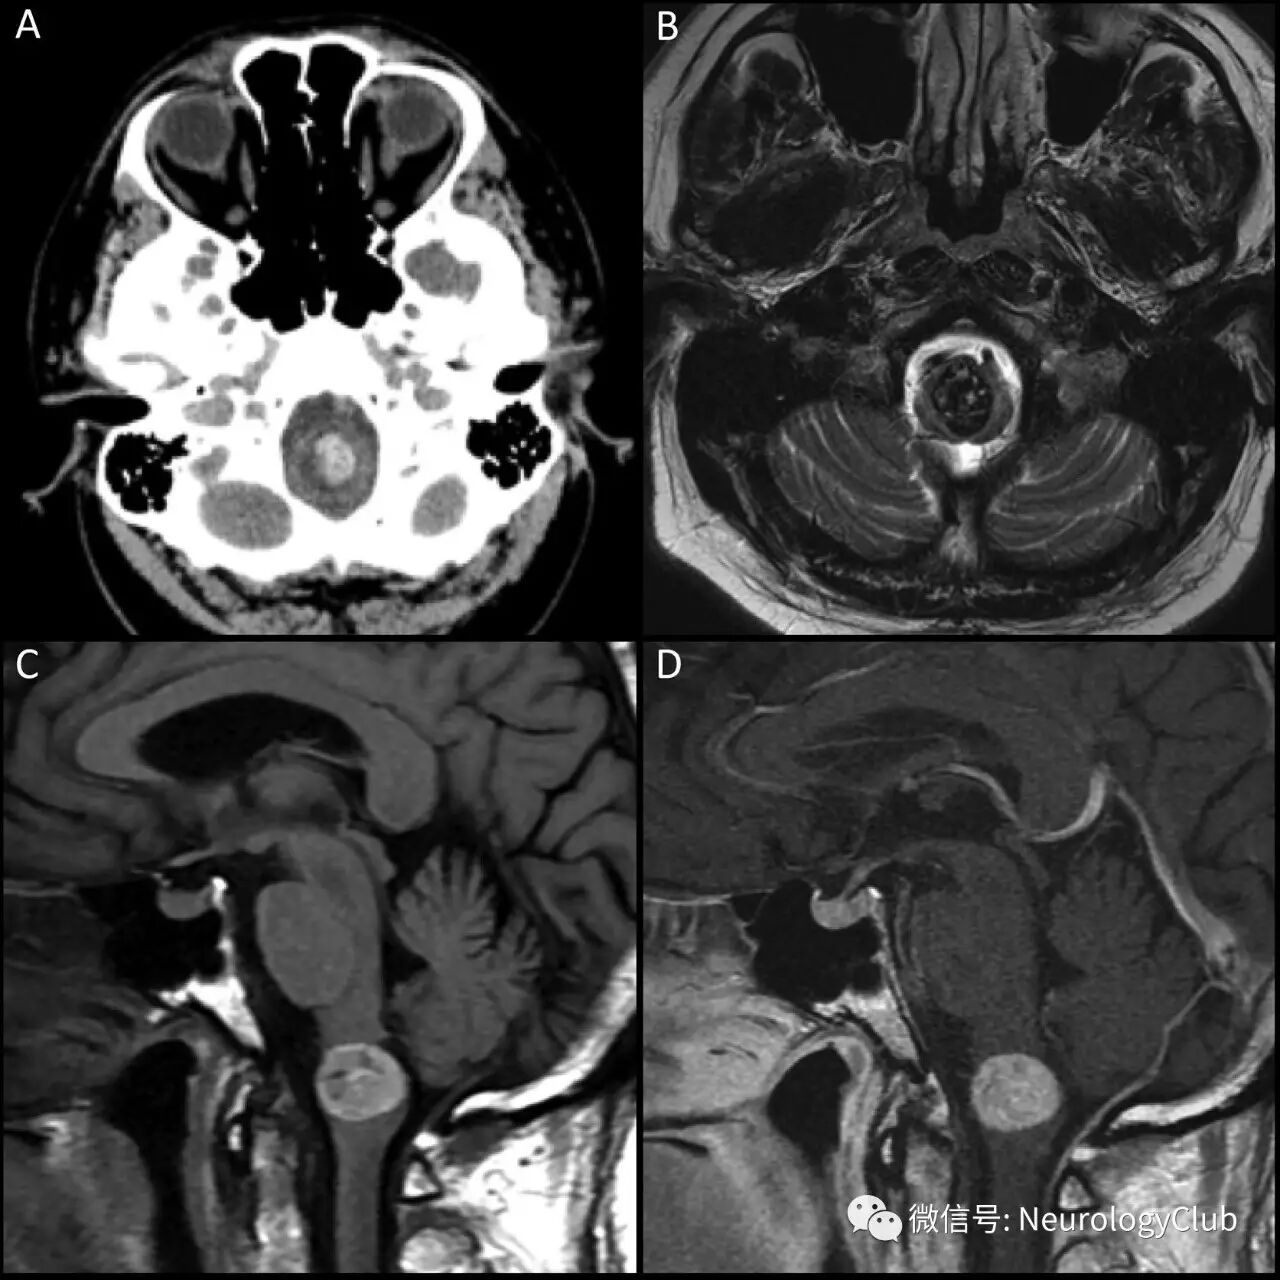

50岁男性,表现为进行性无力,以右上肢明显。最初头颅CT平扫可见直径1.5cm延髓肿块。病灶呈高密度(95Hounsfield单位),后上部可见囊性成分。随后的MRI证实肿块信号不均,主要呈明显的T1高信号和T2低信号,未见确切的强化和异常的弥散受限,尽管高T1和低T2信号可能使得强化和弥散受限评估变得较为困难(图1)。

(图1:A:CT可见延髓内高密度病灶,大小为1.4×1.4×1.6cm;B:T2WI可见病灶以低信号为主;C:T1WI可见下延髓病灶呈不均匀高信号,直径达15mm;D:增强后未见确切强化)